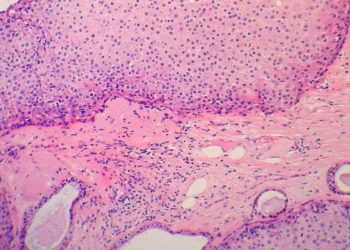

Image: PD